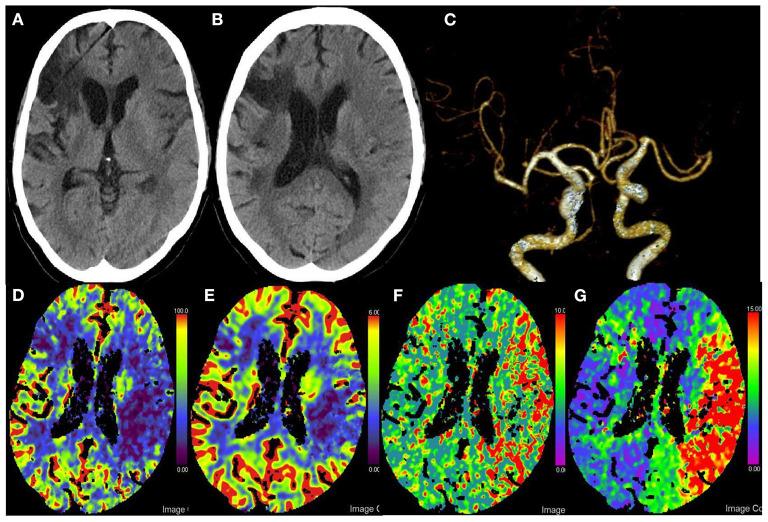

Acute multivessel occlusions generally have multisite clot burden with lower successful reperfusion rates, and cerebrovascular anatomical variants increase the challenge of endovascular clot retrieval. We report a case of acute anterior multivessel occlusions patient with duplicated middle cerebral artery. Combined balloon guide catheter with stent retriever and aspiration approach has gained complete revascularization and good functional outcomes at 3 months follow-up.

急性多血管闭塞通常存在多部位血栓负荷,再灌注成功率较低,而脑血管解剖变异增加了血管内血栓取出的难度。我们报告一例患有双侧大脑中动脉的急性前循环多血管闭塞患者。联合使用球囊导引导管、取栓支架和抽吸方法,在3个月的随访中实现了完全再灌注并取得了良好的功能预后。